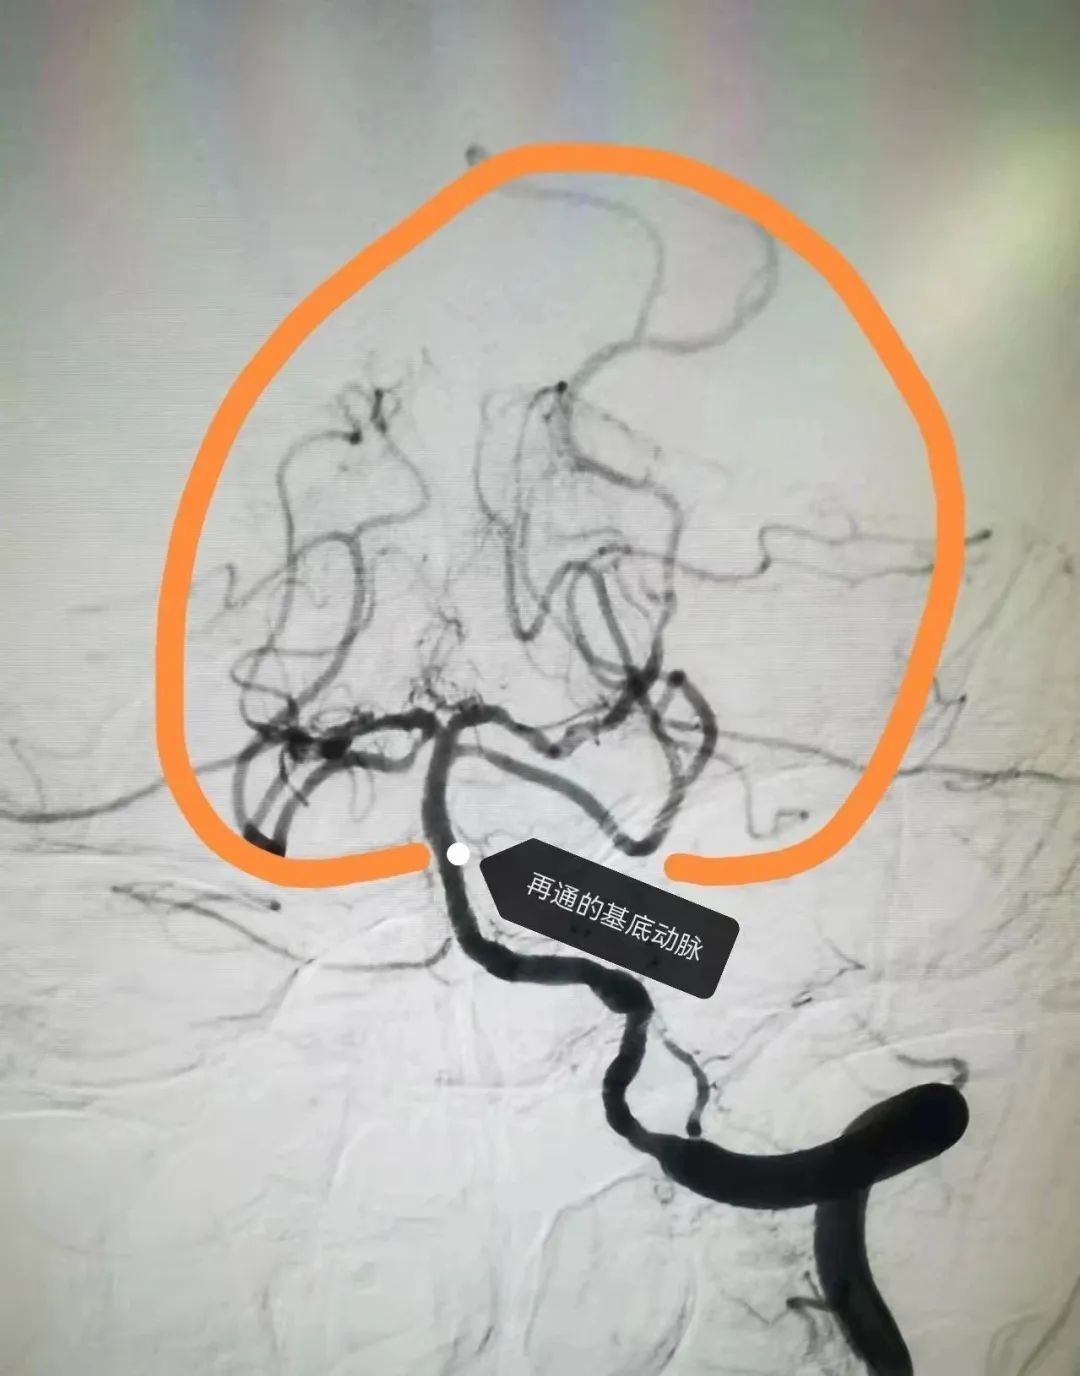

面对如此严峻的病情,神经外科团队当机立断,立即启动了手术绿色通道,准备进行紧急介入手术,以争分夺秒的速度打通栓塞的血管,挽救患者宝贵的生命。在手术过程中,医生们发现刘某的基底动脉栓塞严重,供血区域血管几乎消失无踪。

然而,在神经外科医生们精湛的技术和先进的医疗设备辅助下,手术团队成功运用了Solitaire+Navien抽拉结合取栓技术,一举开通了闭塞的血管。随着血管的重新开通,血流瞬间恢复,手术取得了立竿见影的效果。